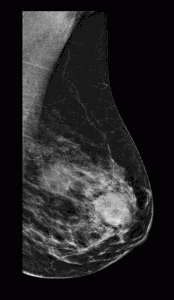

Caso 19

Elena Martinez